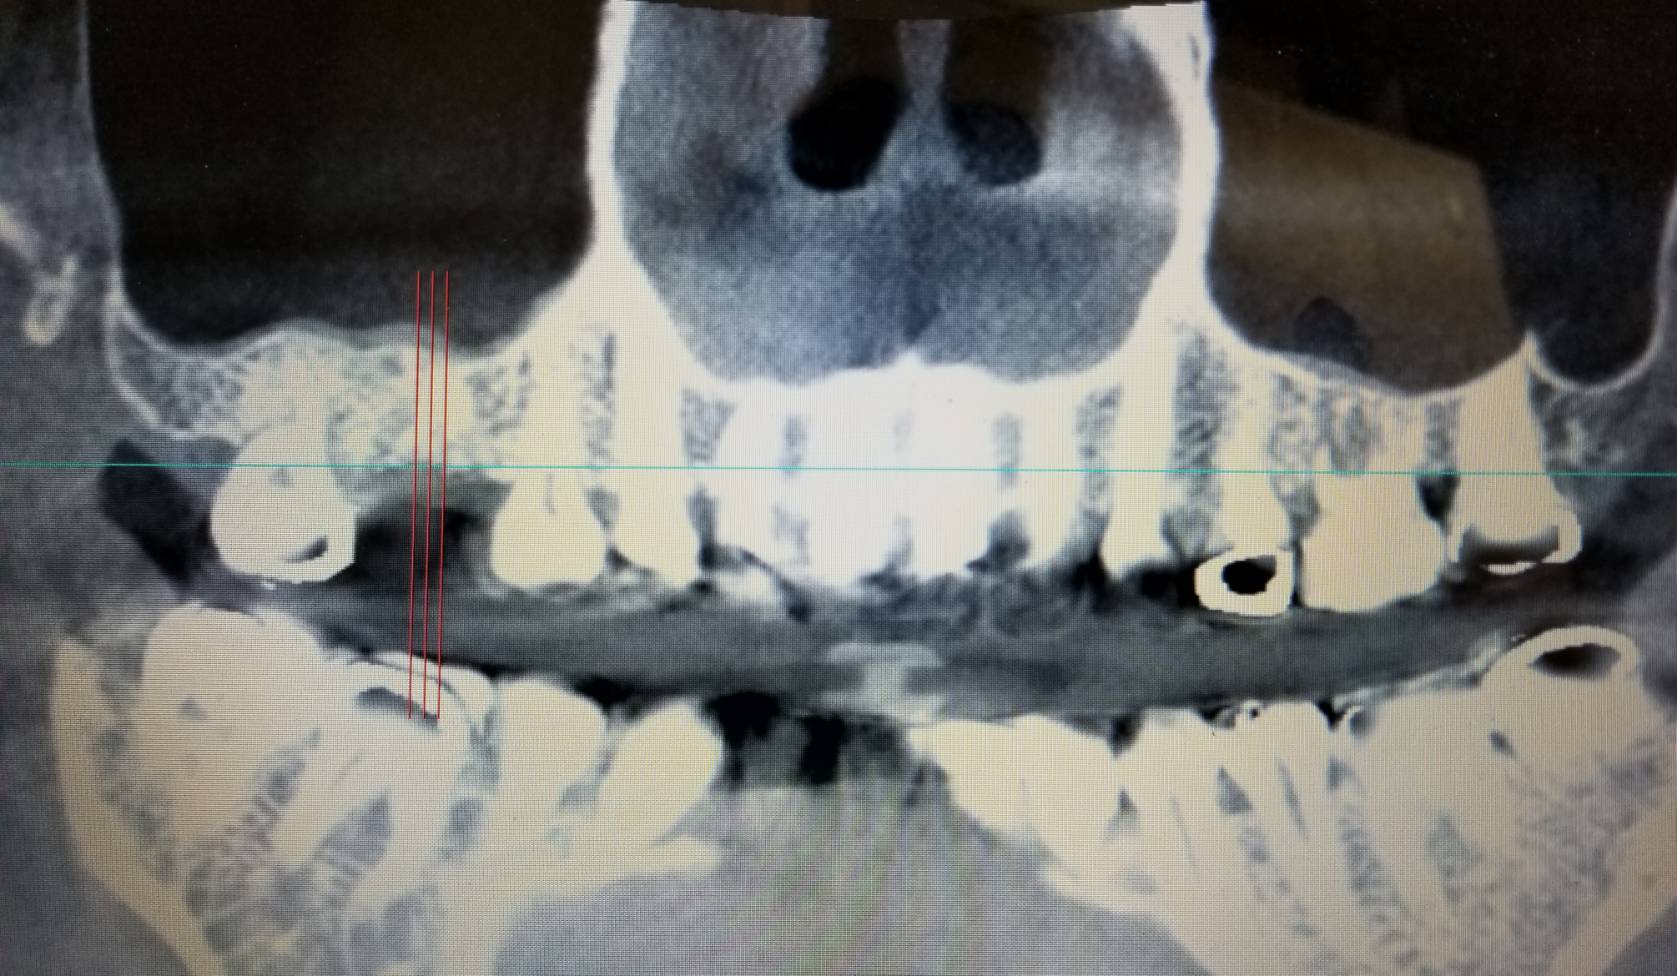

上下顎を正面から全体的に写したものです。

赤の3本線と青の線が交わったところにインプラントを埋めます。